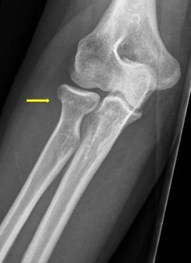

U heeft een kleine breuk van de radiuskop of radiushals. Dit zit in uw spaakbeen ter hoogte van de elleboog. We behandelen deze breuk met een drukverband en een sling. Dit is een soort mitella. Deze breuk herstelt doorgaans zonder restklachten. Daarom maken we geen standaard poliklinische controle afspraak. Het is wel belangrijk dat u na uiterlijk 1 week uw verband en sling verwijdert en start met oefenen om stijfheid van de elleboog te voorkomen. Geschikte oefeningen vindt u in deze folder.

Een gebroken radiuskop of radiushals komt vaak voor. Dit is goed te behandelen met een drukverband en een sling (mitella). Na 1 week begint u met oefeningen.